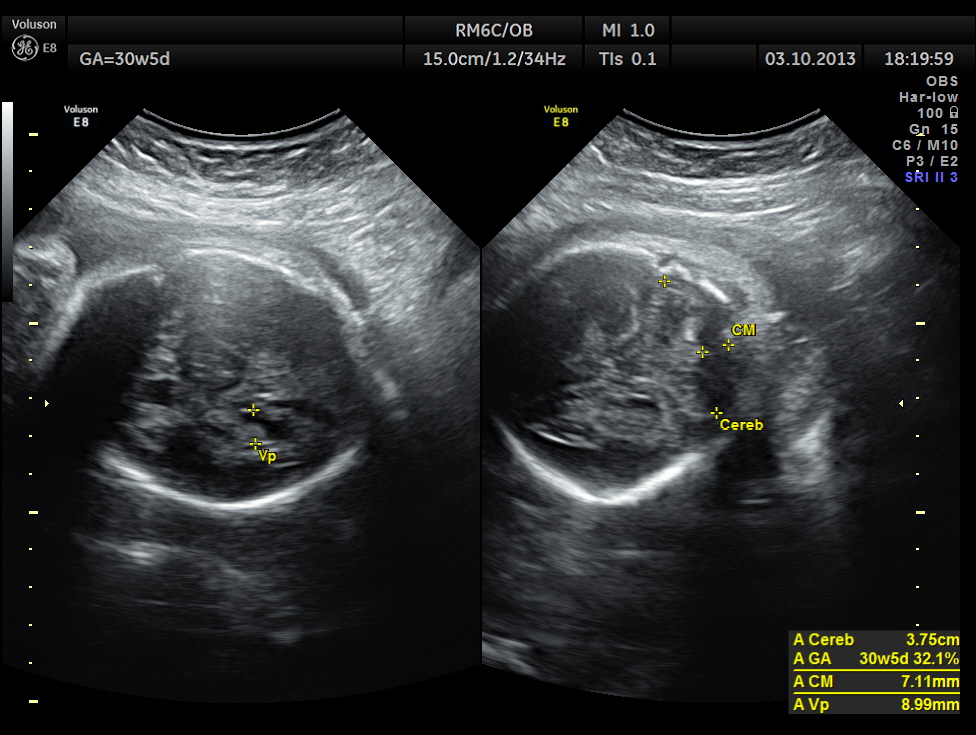

The cerebellum shows 32.1 % tile growth.